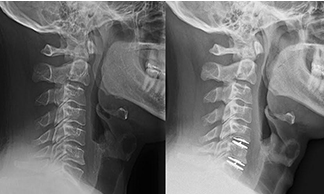

This gentleman had neck and arm pain that failed years of nonoperative treatment. He was back to his normal routine without pain a few days after surgery. Read More